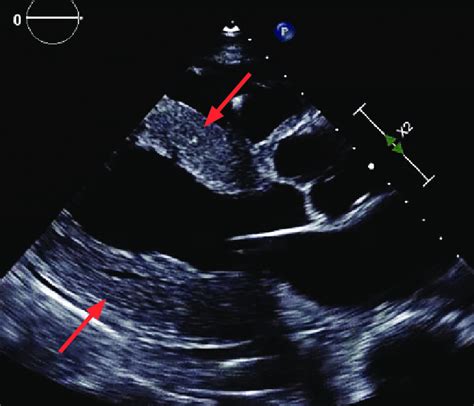

The long axis view, especially the parasternal long axis (PLAX) view, is a cornerstone in echocardiography. Guys, think of it as the money shot! This view allows us to visualize key structures like the left ventricle, right ventricle, aortic valve, mitral valve, and the left atrium all in one go. With this comprehensive view, clinicians can assess heart valve function, measure chamber sizes, and evaluate the overall systolic and diastolic function of the heart. For example, being able to see the mitral valve clearly helps in diagnosing mitral stenosis or regurgitation. Similarly, a good view of the aortic valve is essential for identifying aortic stenosis or aortic insufficiency. Furthermore, the long axis view is crucial for detecting structural abnormalities such as hypertrophic cardiomyopathy or dilated cardiomyopathy. By measuring the thickness of the ventricular walls and assessing the size of the chambers, clinicians can gain valuable insights into the heart’s condition. In emergency situations, the PLAX view can quickly provide information about pericardial effusions or cardiac tamponade, guiding immediate treatment decisions. So, yeah, mastering this view is a big deal for accurate diagnoses and effective patient care.

Alright, let’s get down to the nitty-gritty of long axis view echo probe position . The standard approach starts with placing the probe in the third or fourth intercostal space, just to the left of the sternum. Now, here’s the kicker: the orientation marker on your probe (usually a notch or a light) should be pointing towards the patient’s right shoulder. This is crucial because it aligns the ultrasound beam in the correct plane to capture the long axis view of the heart. Once you’ve placed the probe, start by fanning and tilting it slightly. Fanning involves making small, sweeping motions from side to side, while tilting means angling the probe up or down. These subtle adjustments can make a huge difference in image quality. You’re essentially hunting for the best acoustic window – the spot where the ultrasound waves can penetrate the chest wall with minimal obstruction. When you find that sweet spot, you should see the left ventricle appearing as an elongated chamber with the mitral valve opening and closing. The aortic valve will be visible at the top of the left ventricle, and the left atrium will be behind the mitral valve. Don’t worry if it doesn’t look perfect right away. It takes practice and a bit of finesse to get it just right. Keep adjusting the probe position and angle until you get a clear and comprehensive view of all the key structures. Remember, patience is key, and every patient’s anatomy is a little different, so be prepared to adapt your technique as needed.